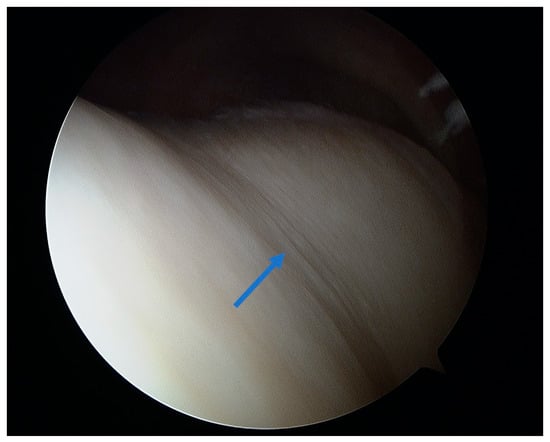

Figure 3.

Arthroscopic view of healthy cartilage on the medial femoral condyle (asterisk) and grade I lesion on the medial tibial condyle with visible superficial layer fibrillation (arrow).